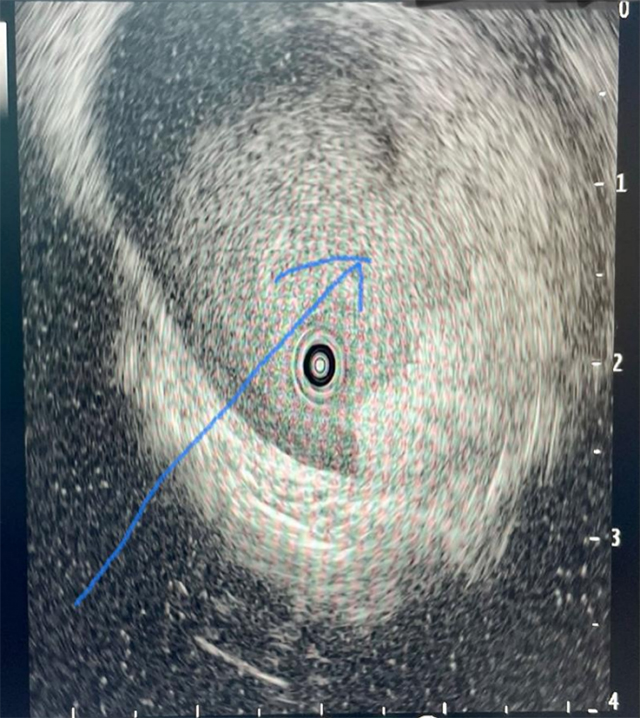

完全经自然腔道的胆囊内超声成像显示胆囊肿瘤性病变(箭头)

该检查属于完全经自然腔道的超微创手术,即十二指肠镜下超细内镜和胆道内超声探头经口腔→食管→胃→十二指肠→胆总管→胆囊等人体自然腔道到达胆囊和胆管内,进行光学直视诊断和超声诊断。最终,患者明确诊断为早期胆囊管腺癌、胆囊颈体部息肉(癌前病变)、胆总管及肝内胆管无异常,纠正了之前其它影像报告的错误诊断。